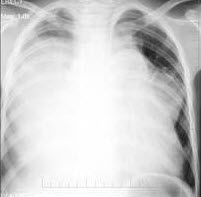

76、单项选择题

男,8岁,胸闷、气急1月余,查体见颈静脉显露,胸片如图,最可能的诊断是()

A.心包积液

B.心肌炎

C.淋巴瘤

D.房间隔缺损

E.肺静脉异位引流